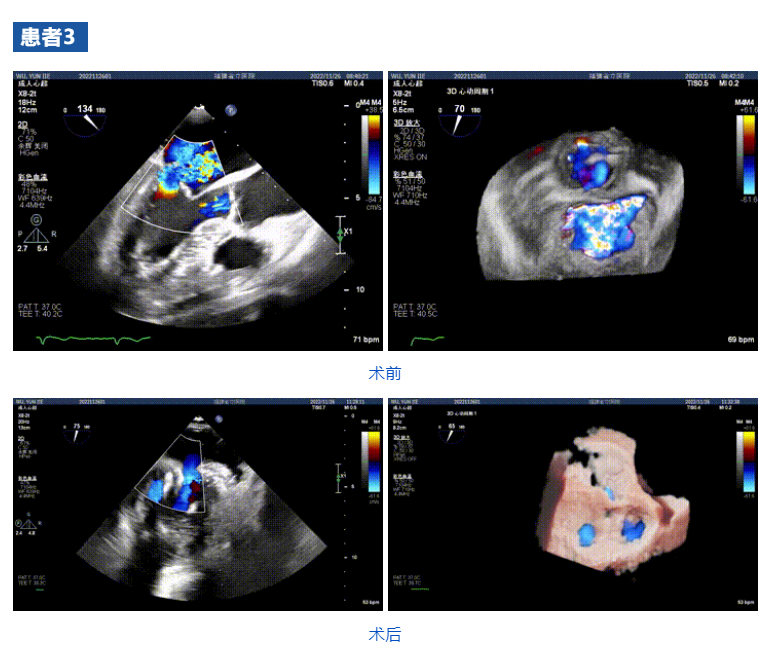

接受治療的三例患者均為器質性重度二尖瓣反流(DMR)患者,術前超聲提示二尖瓣后葉脫垂伴4+反流,左室舒張功能減退。郭延松教授攜同團隊成員陳新敬副教授和洪景宣、方明程、楊清勇主治醫師、心外科丁杭主任以及超聲科賴寶春、葉振盛主治醫師共同進行病情討論。考慮到患者高齡、基礎疾病多、STS評分高,為外科手術極高危患者,不適合進行外科開胸二尖瓣手術,因此決定為患者實施經導管緣對緣修復介入術(JensClip經導管瓣膜夾系統)。

在浙江大學醫學院附屬第二醫院王建安教授團隊的支持下,手術經股靜脈-房間隔入路,采用全身麻醉插管,在TEE和DSA引導下完成房間隔穿刺。置入JensClip瓣膜夾系統后,在左房調整瓣膜夾的位置和軸向,后進入左室,在TEE引導下捕捉二尖瓣前后瓣葉,并關閉瓣膜夾。經TEE反復確認手術效果后最終鎖定并釋放瓣膜夾。術后即刻超聲顯示瓣膜夾位置穩定,功能良好,二尖瓣反流由術前4+減少至微量,手術圓滿成功。